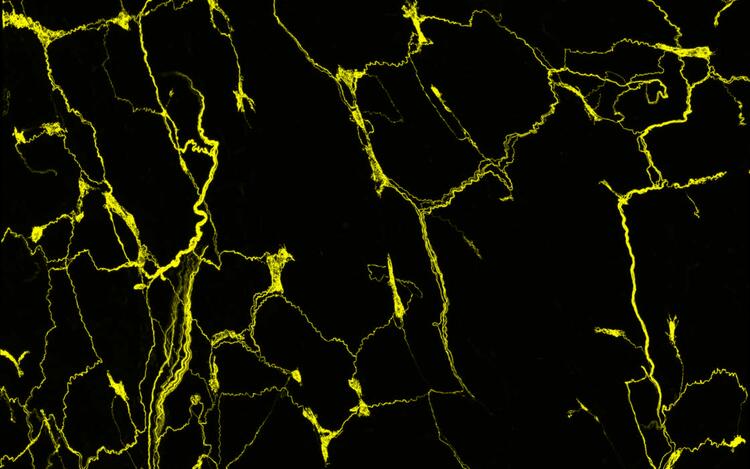

The axons of the sensory neurons form an intricate network in the mouse esophagus. The axonal projections of the sensory neurons, which originate in a ganglion of the vagus nerve (vagal ganglion), are stained with a fluorescent dye. A confocal microscope renders them visible.

© Elijah D. Lowenstein, AG C. Birchmeier, Max Delbrück Center